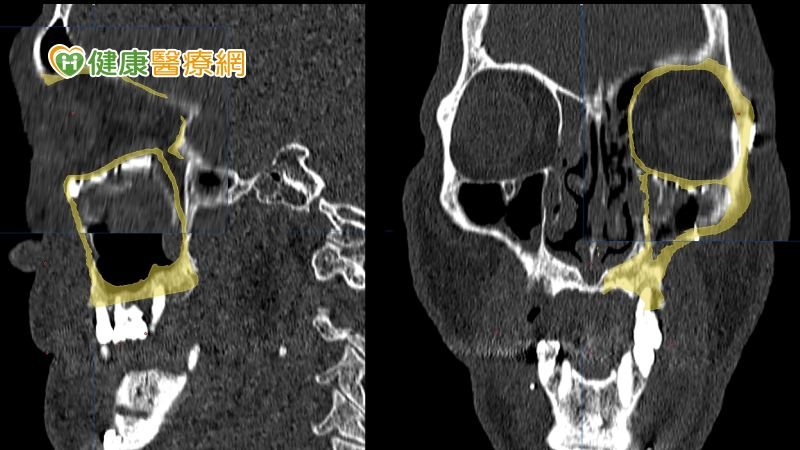

在術前醫師會先透過電腦斷層模擬病人顏面骨骼,並設計出貼近病人原始骨頭構造的立體結構,再利用3D列印技術客製化眼眶骨及顴骨模型,預先調整眼底鈦合金骨板的形狀。黃子桓醫師表示,這不僅能精確地重建,也可以節省手術時間,並提升成功率避免二次手術的可能。

不過,黃子桓醫師提到,如果是已在錯誤位置癒合的顏面骨骨折,重建手術會更為複雜,切斷已癒合的骨塊後,要在立體空間中將骨塊移動到理想位置其實並不容易,在沒有導航的幫助下,手術的不確定性會很高,若術中同步利用導航輔助定位,將能大幅提高精確性。

因此,醫療團隊在術前為李先生模擬、設計精確的復位計畫後,術中也同步利用導航系統協助定位,將錯位的骨塊逐步復位至理想的位置。黃子桓醫師表示,李先生在經過手術後,恢復良好的咬合關係及左右顏面對稱性,住院一週便順利出院。